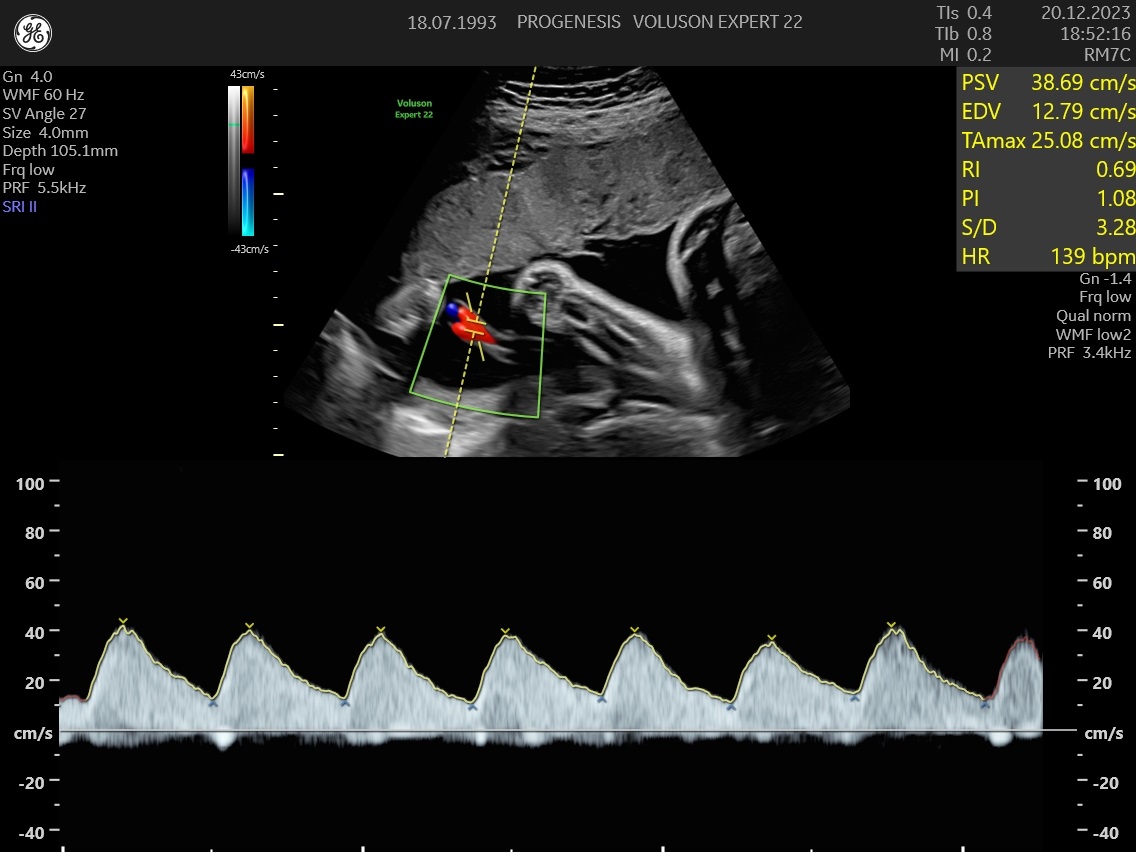

Ελέγχεται επίσης η παροχή οξυγόνου από της αρτηρίες της μητέρας στη μήτρα (Doppler μητριαίων αγγείων), από τον ομφάλιο λώρο στο έμβρυο (Doppler ομφαλικής αρτηρίας) καθώς και η ροή στην κεντρική αρτηρία του εγκεφάλου.